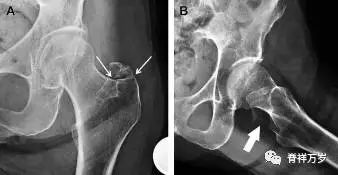

9股骨外侧髁凹陷征

图 2 扭伤后的股骨外侧髁凹陷征

A 侧位片示股骨外侧髁凹陷。B MRI 矢状位 T2 加权像示股骨外侧髁及胫骨后外侧骨挫伤(空箭头)。胫骨近端随着后交叉韧带撕裂发生移位,露出外侧半月板的后角(弧形箭头)。